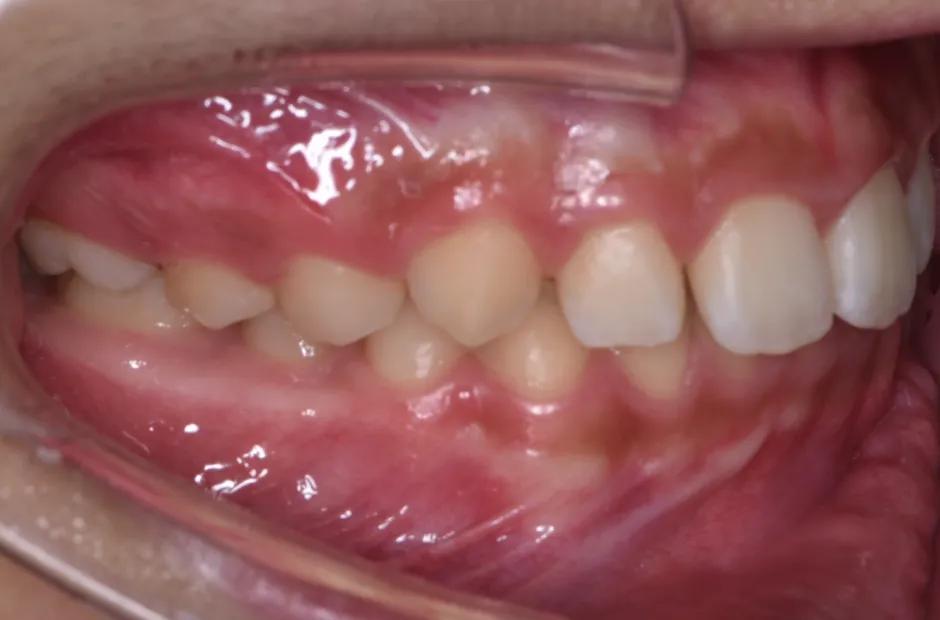

| 診断名・主訴 | 出っ歯 |

|---|---|

| 年齢・性別 | 16歳・男性 |

| 治療期間・回数 | 1年4か月 |

| 治療に用いた主な装置 | ブラケット |

| 抜歯部位 | 上顎4,4 |

| 治療費 | 60万円(税抜) |

| リスク・副作用 | 装置による違和感・疼痛・歯肉退縮・歯根吸収・虫歯のリスクなど |

治療前

治療後